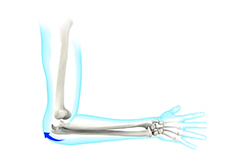

Cubital Tunnel Syndrome (Ulnar Nerve Entrapment)

When the elbow is bent, the ulnar nerve can stretch and catch on the bony bump. When the ulnar nerve is compressed or entrapped, the nerve can tear and become inflamed, leading to cubital tunnel syndrome.